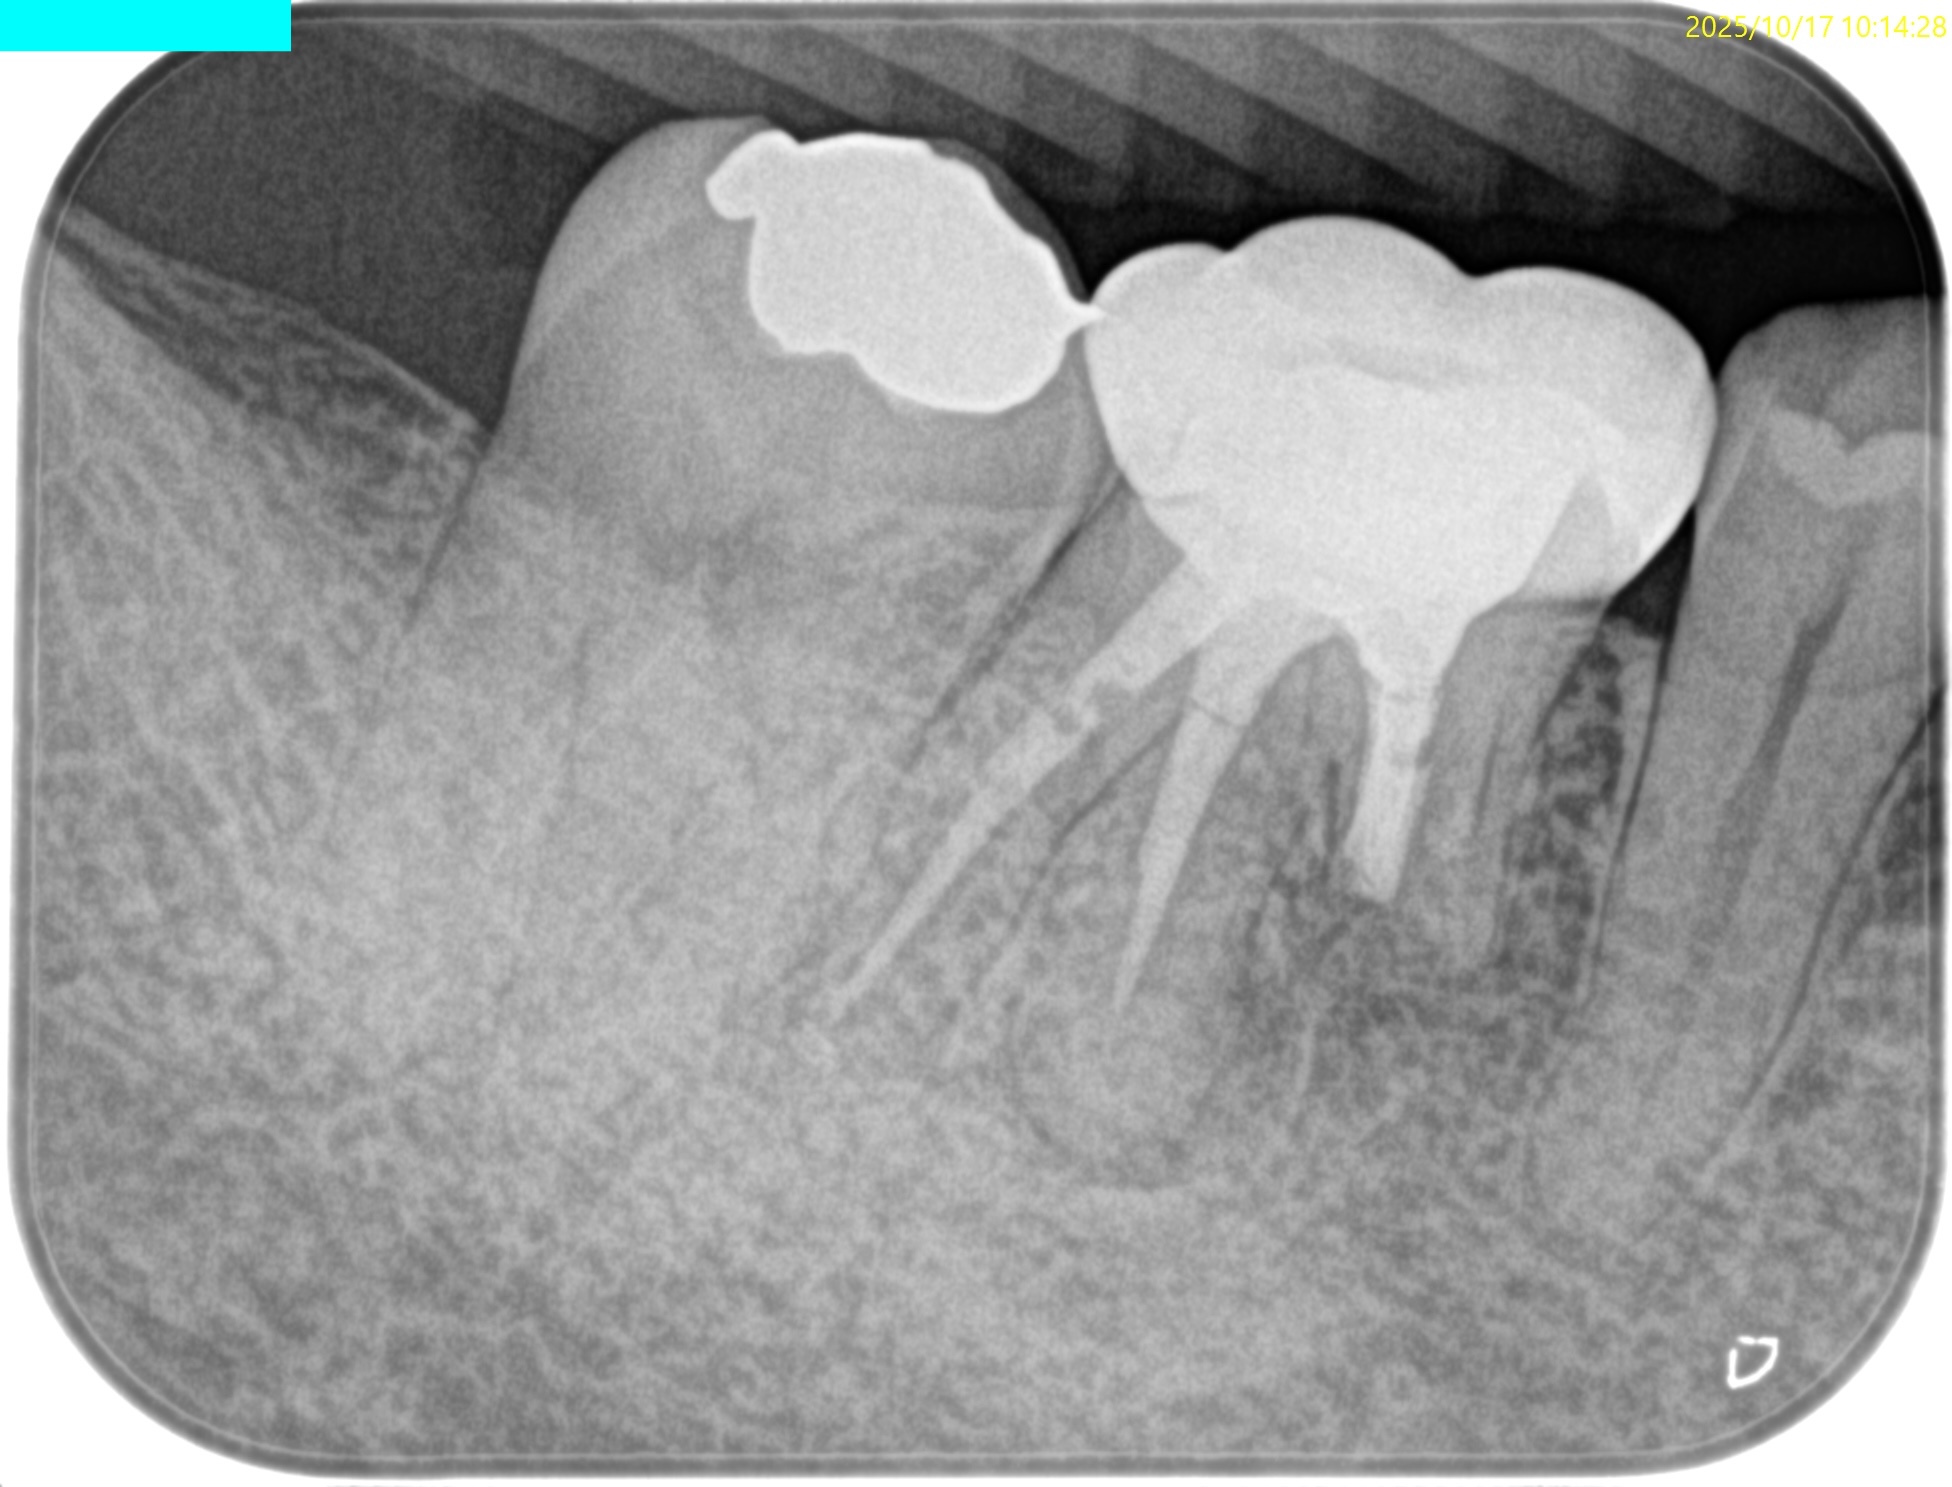

#30 M Apicoectomy, D+Radix Re-RCT 2yr recall(2025.10.17)

D

初診時、1年後と比較した。

トランスポーテーションしたMは劇的に治癒している。

Dも然りだ。

が、トランスポーテーションしているRadixはまだ治癒途中だろう。

が、患者さんに症状もないことからこの歯の状況はさらに2年後に経過を見せてもらうこととなった。